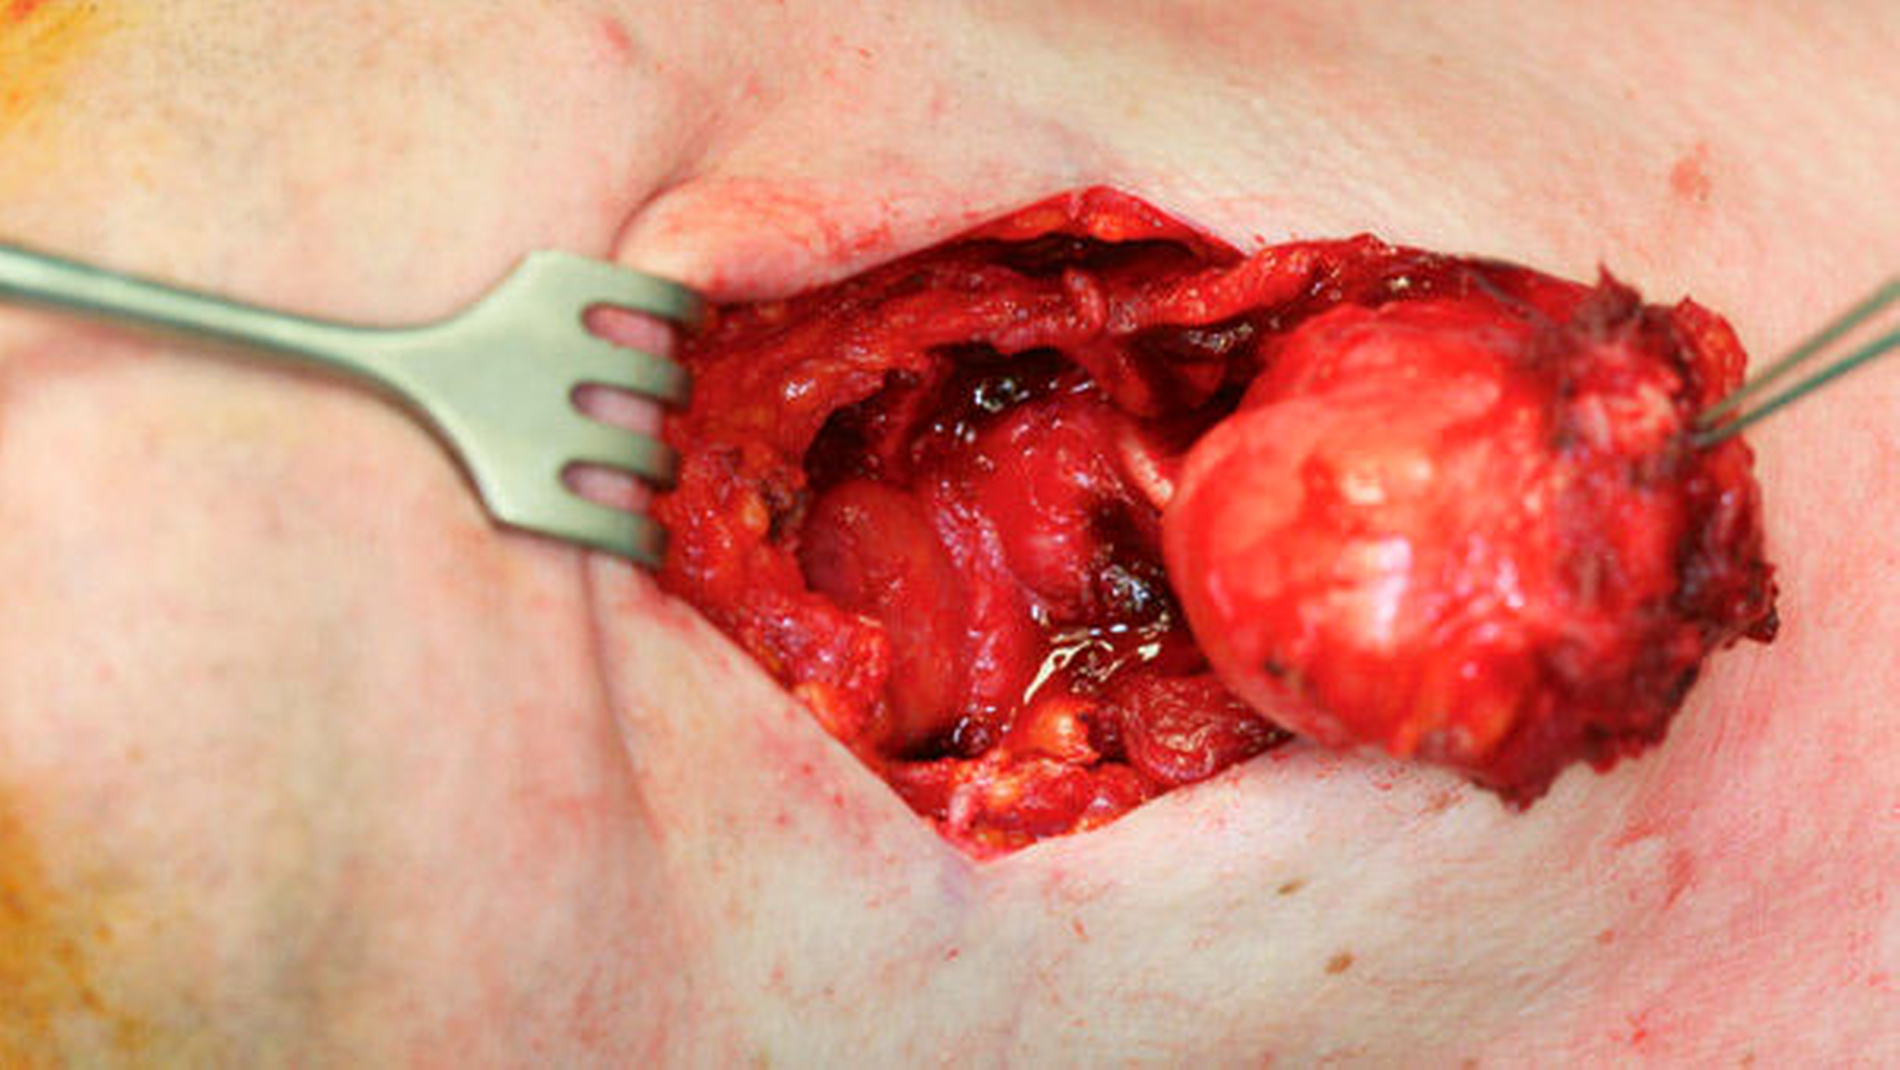

Durch die Befunde der anamnestischen, klinischen und MRT-Untersuchungen konnte die Diagnose einer medianen Halszyste gesichert werden. Die operative Entfernung der zervikalen Raumforderung wurde anschließend mit dem Patienten vereinbart und dann in Allgemeinnarkose über einen extraoralen Zugang durchgeführt (Abbildung 3a). Bei der intraoperativen Enukleation des zystisch imponierenden Gewebes konnte die Verbindung zum Os hyoideum eindeutig dargestellt werden (Abbildung 3b). Das raumfordernde Gewebe wurde dann mit dem gesamten medianen Anteil des Zungenbeins durch kontinuitätsunterbrechende Resektion entfernt (Abbildung 3c). Die feingewebliche Begutachtung des entnommenen Gewebes bestätigte in den histopathologischen Präparaten die klinisch und radiologisch gesicherte Diagnose einer medianen Halszyste (Abbildung 4).